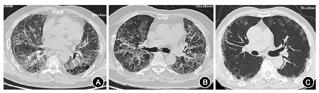

胸部X线检查可排除气胸或其他需要立即处理的胸部异常情况。胸部HRCT可准确显示肺实质异常的形态及部位,并可进一步对AE-IPF的影像学表现进行分类[9,31]。AE-IPF患者HRCT显示在典型UIP型[如网状影、牵拉性支气管和(或)细支气管扩张及蜂窝改变]的背景上,出现新的GGO和(或)实变影[9](图1)。AE-IPF患者胸部HRCT新增异常阴影可表现为3种类型:弥漫型、多灶型和周边型[31](图2)。

注:A为弥漫型,双肺弥漫性GGO、斑片状实变和胸膜下蜂窝影;B为多灶型,在胸膜下蜂窝和牵拉性支气管扩张背景上出现双肺中心和外周多处分布斑片状GGO;C为周边型,双肺外周分布GGO和胸膜下蜂窝影。GGO为磨玻璃影